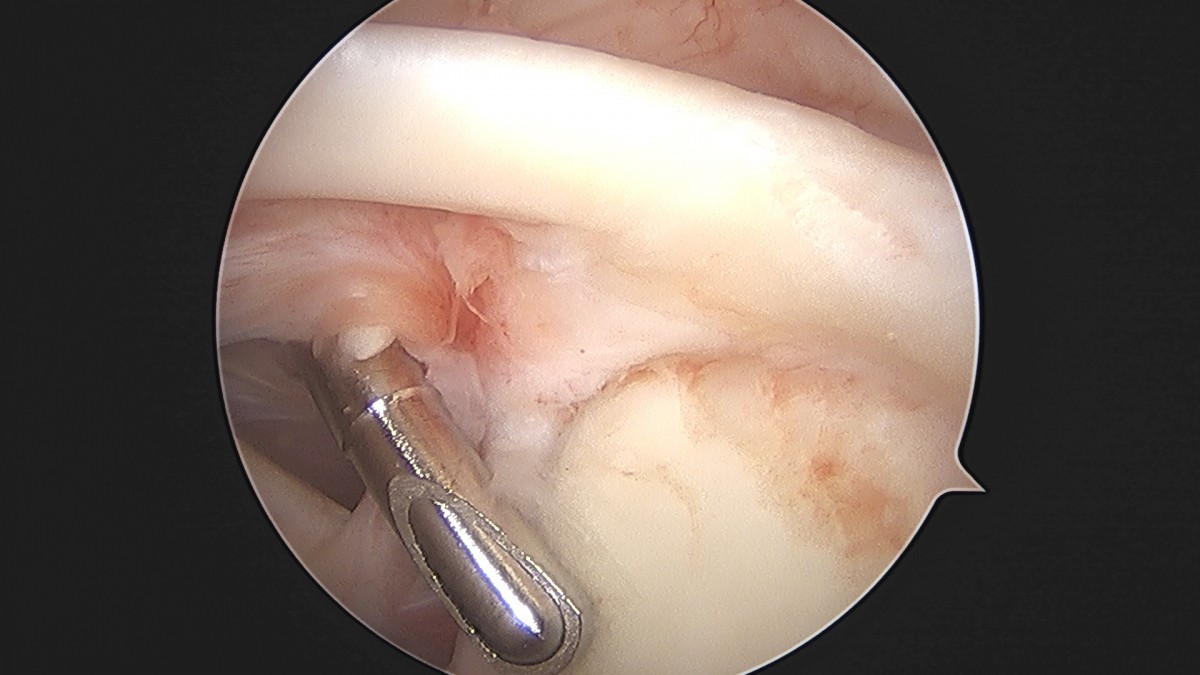

정지영원장님 어깨 관절낭 이완술 이상O 환자

작성자 최고관리자 댓글 0건 조회 743회 작성일 25-09-16 16:58